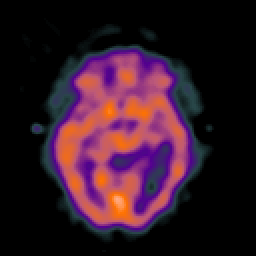

SPECT TC Study #5 -- Slice #25

[Home][Help][Clinical][Tour 1][Tour 2][Tour 3] Slice 25